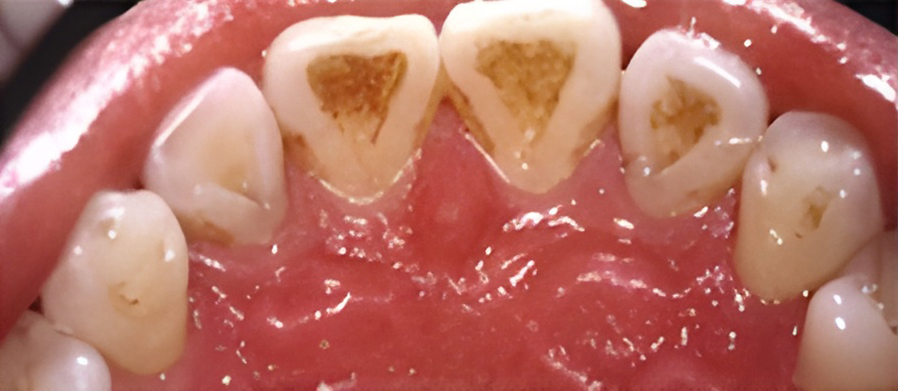

If you have signs of unhealthy gums such as redness, swelling, bleeding, tenderness, and bad breath, our doctor may recommend root planing and curettage. Root planing and curettage smooth the root surfaces beneath the gum line to remove plaque and calculus, and remove inflamed tissue so that healthy gum tissue may heal next to the cleaned and smooth tooth surface.

Because this procedure goes deeper than regular teeth cleaning, local anesthetic is needed to numb the gum.

Two office visits are usually required to complete the procedure.

The primary cause of periodontal disease is the accumulation of bacterial plaque at and under the gum line.

If plaque is not removed daily through brushing and flossing, the bacteria will cause the gum tissue to become red and swollen. At this first stage, gingivitis can and may be reversed by visiting your dentist and dental hygienist, along with your efforts at maintaining good dental hygiene.

If gingivitis is left untreated, the plaque can spread to the roots, causing an infection and damage to the supporting bone and soft tissue. The gums may separate from the tooth and start to recede. A pocket can form below the gum line and trap plaque and food. As periodontitis progresses, up to one-third of the bone can be lost.

In this later stage, half or more of the original bone holding the tooth is lost, and the pocket becomes very deep. The gums recede even more and the tooth may appear longer because the root is exposed. The tooth may eventually fall out due to a lack of supporting bone.